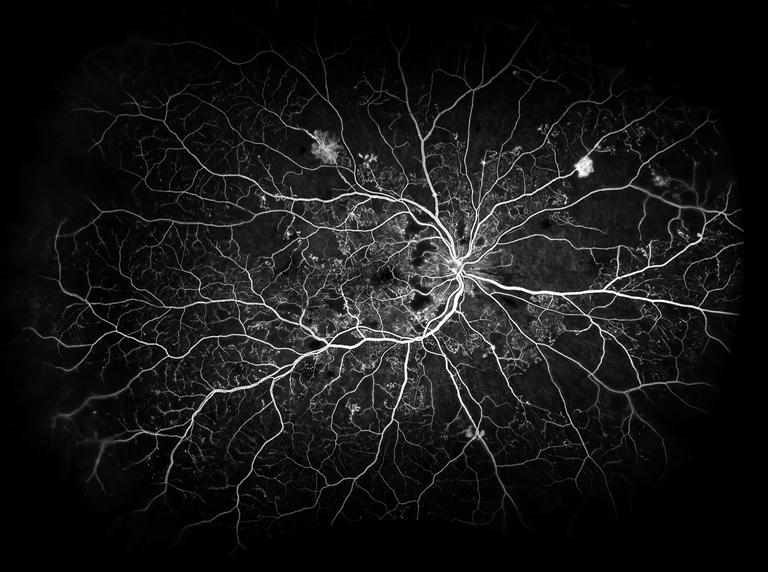

Type 1 Diabetic Retinopathy

Presented by Judith Gulian, BSc, OCT-CThis photograph received 2nd Place in the category "Retinal Fluorescein Angiography" and was displayed at the 2024 ASCRS/OPS Society Exhibit.